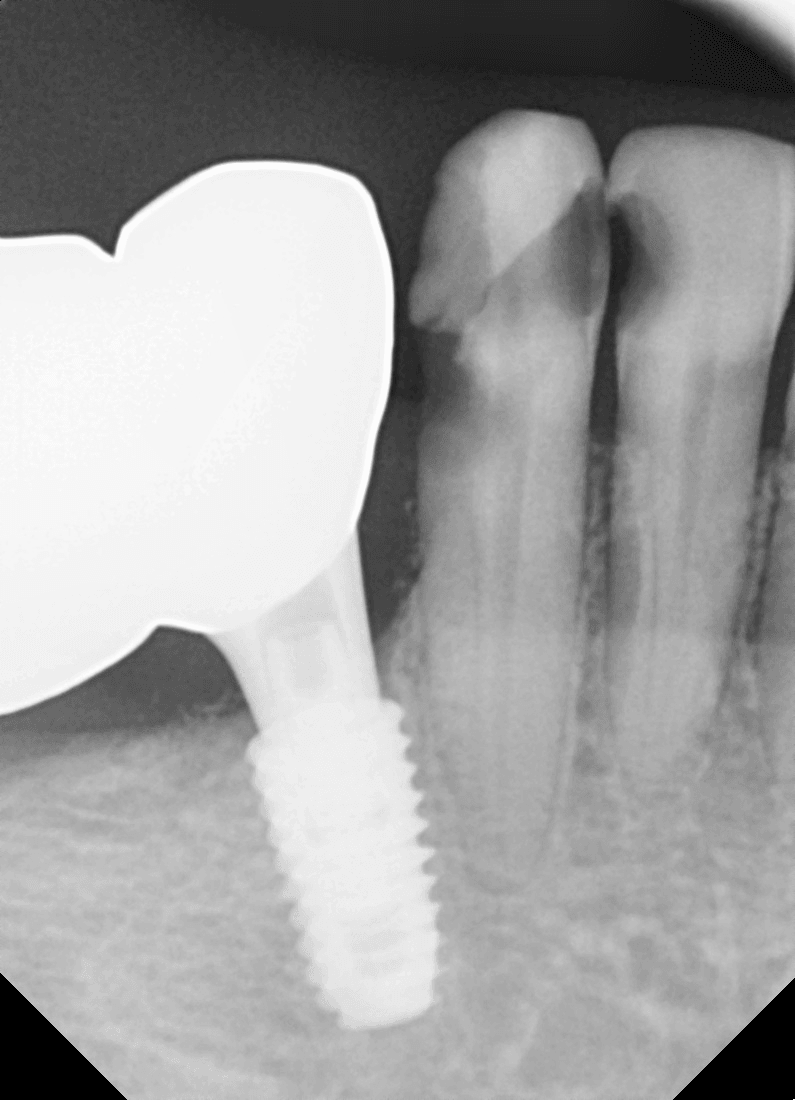

양치할 때 피가 나오는 출혈은 잇몸염증의 대표적인 신호입니다.

출혈은 이미 잇몸에 염증이 있다는 뜻입니다.

하지만 방치하면 치주염으로 진행됩니다.

치주염이 되면 치조골이 녹기 시작합니다.

이때부터는 치아 흔들림이 생깁니다.

치석 제거와 치주치료가 필요합니다.